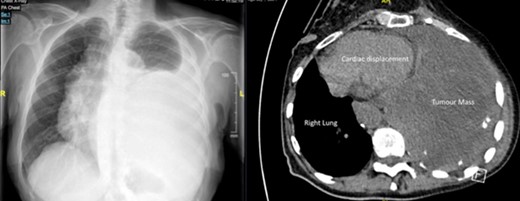

A 92-year-old, previously independent female presented acutely with severe resting dyspnoea, exercise tolerance of less than fifty metres—limited by dyspnoea and presyncope, orthopnoea, peripheral oedema and early satiety. Complete whiteout of left mid-to-lower zones with accompanying mediastinal shift was seen on initial chest X-ray (Fig 1b). CT chest performed in view of these findings demonstrated a giant (130 × 133 × 147 mm) posterior mediastinal mass arising from the left T10/T11 foramina, and causing significant cardiac displacement and complete collapse of left lower lobe and lingula (Fig 1b). Ventilation-perfusion scan showed a matched defect affecting the entire lower lobe and lingula. Percutaneous biopsy of the mass demonstrated a schwannoma (Fig 2).